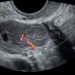

Anche a Dicembre un nuovo Journal Club relativo ad un nuovo segno ecografico in caso di Placenta Acc